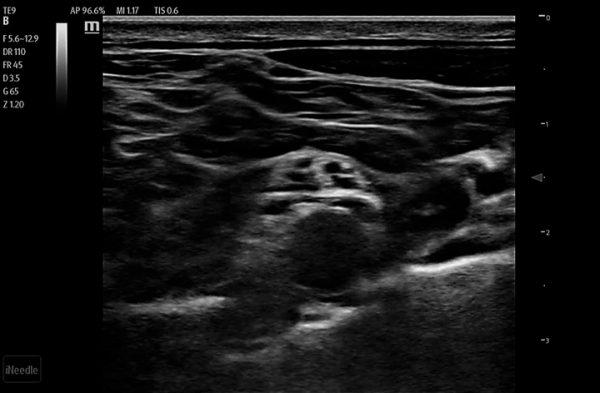

Needle Guidance

Clinical Images